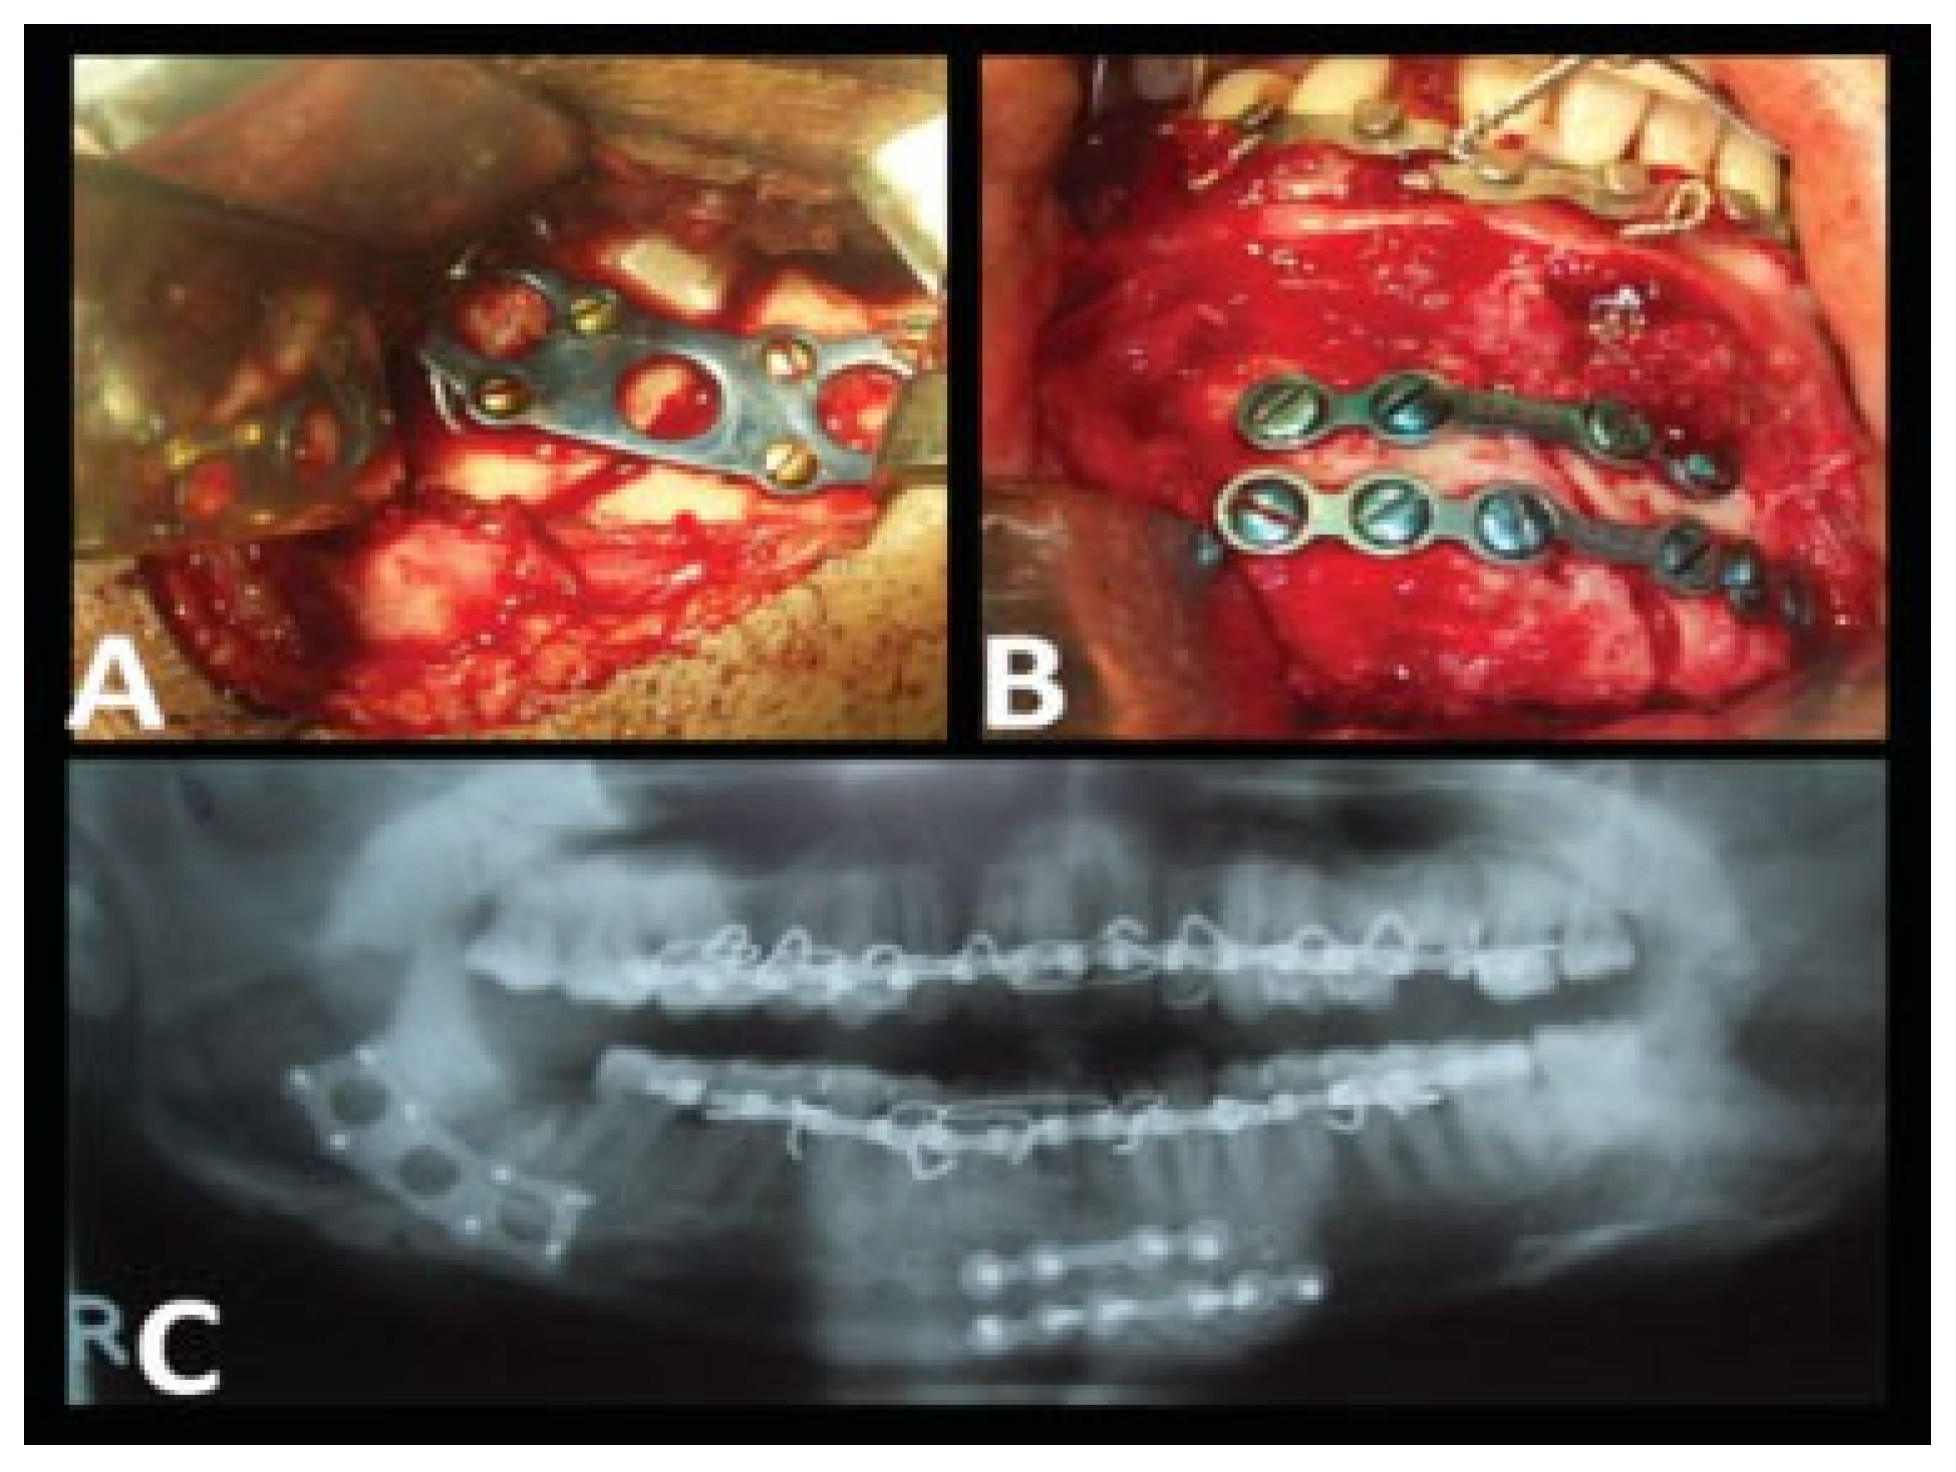

Evaluation of 2.0-mm Titanium Three-Dimensional Curved Angle Strut Plate in the Fixation of Mandibular Angle Fractures—A Prospective Clinical and Radiological Analysis

Chhabaria, G.; Halli, R.; Chandan, S.; Joshi, S.; Setiya, S.; Shah, A. Evaluation of 2.0-mm Titanium Three-Dimensional Curved Angle Strut Plate in the Fixation of Mandibular Angle Fractures—A Prospective Clinical and Radiological Analysis. Craniomaxillofac. Trauma Reconstr. 2014, 7, 119-125. https://doi.org/10.1055/s-0034-1371002